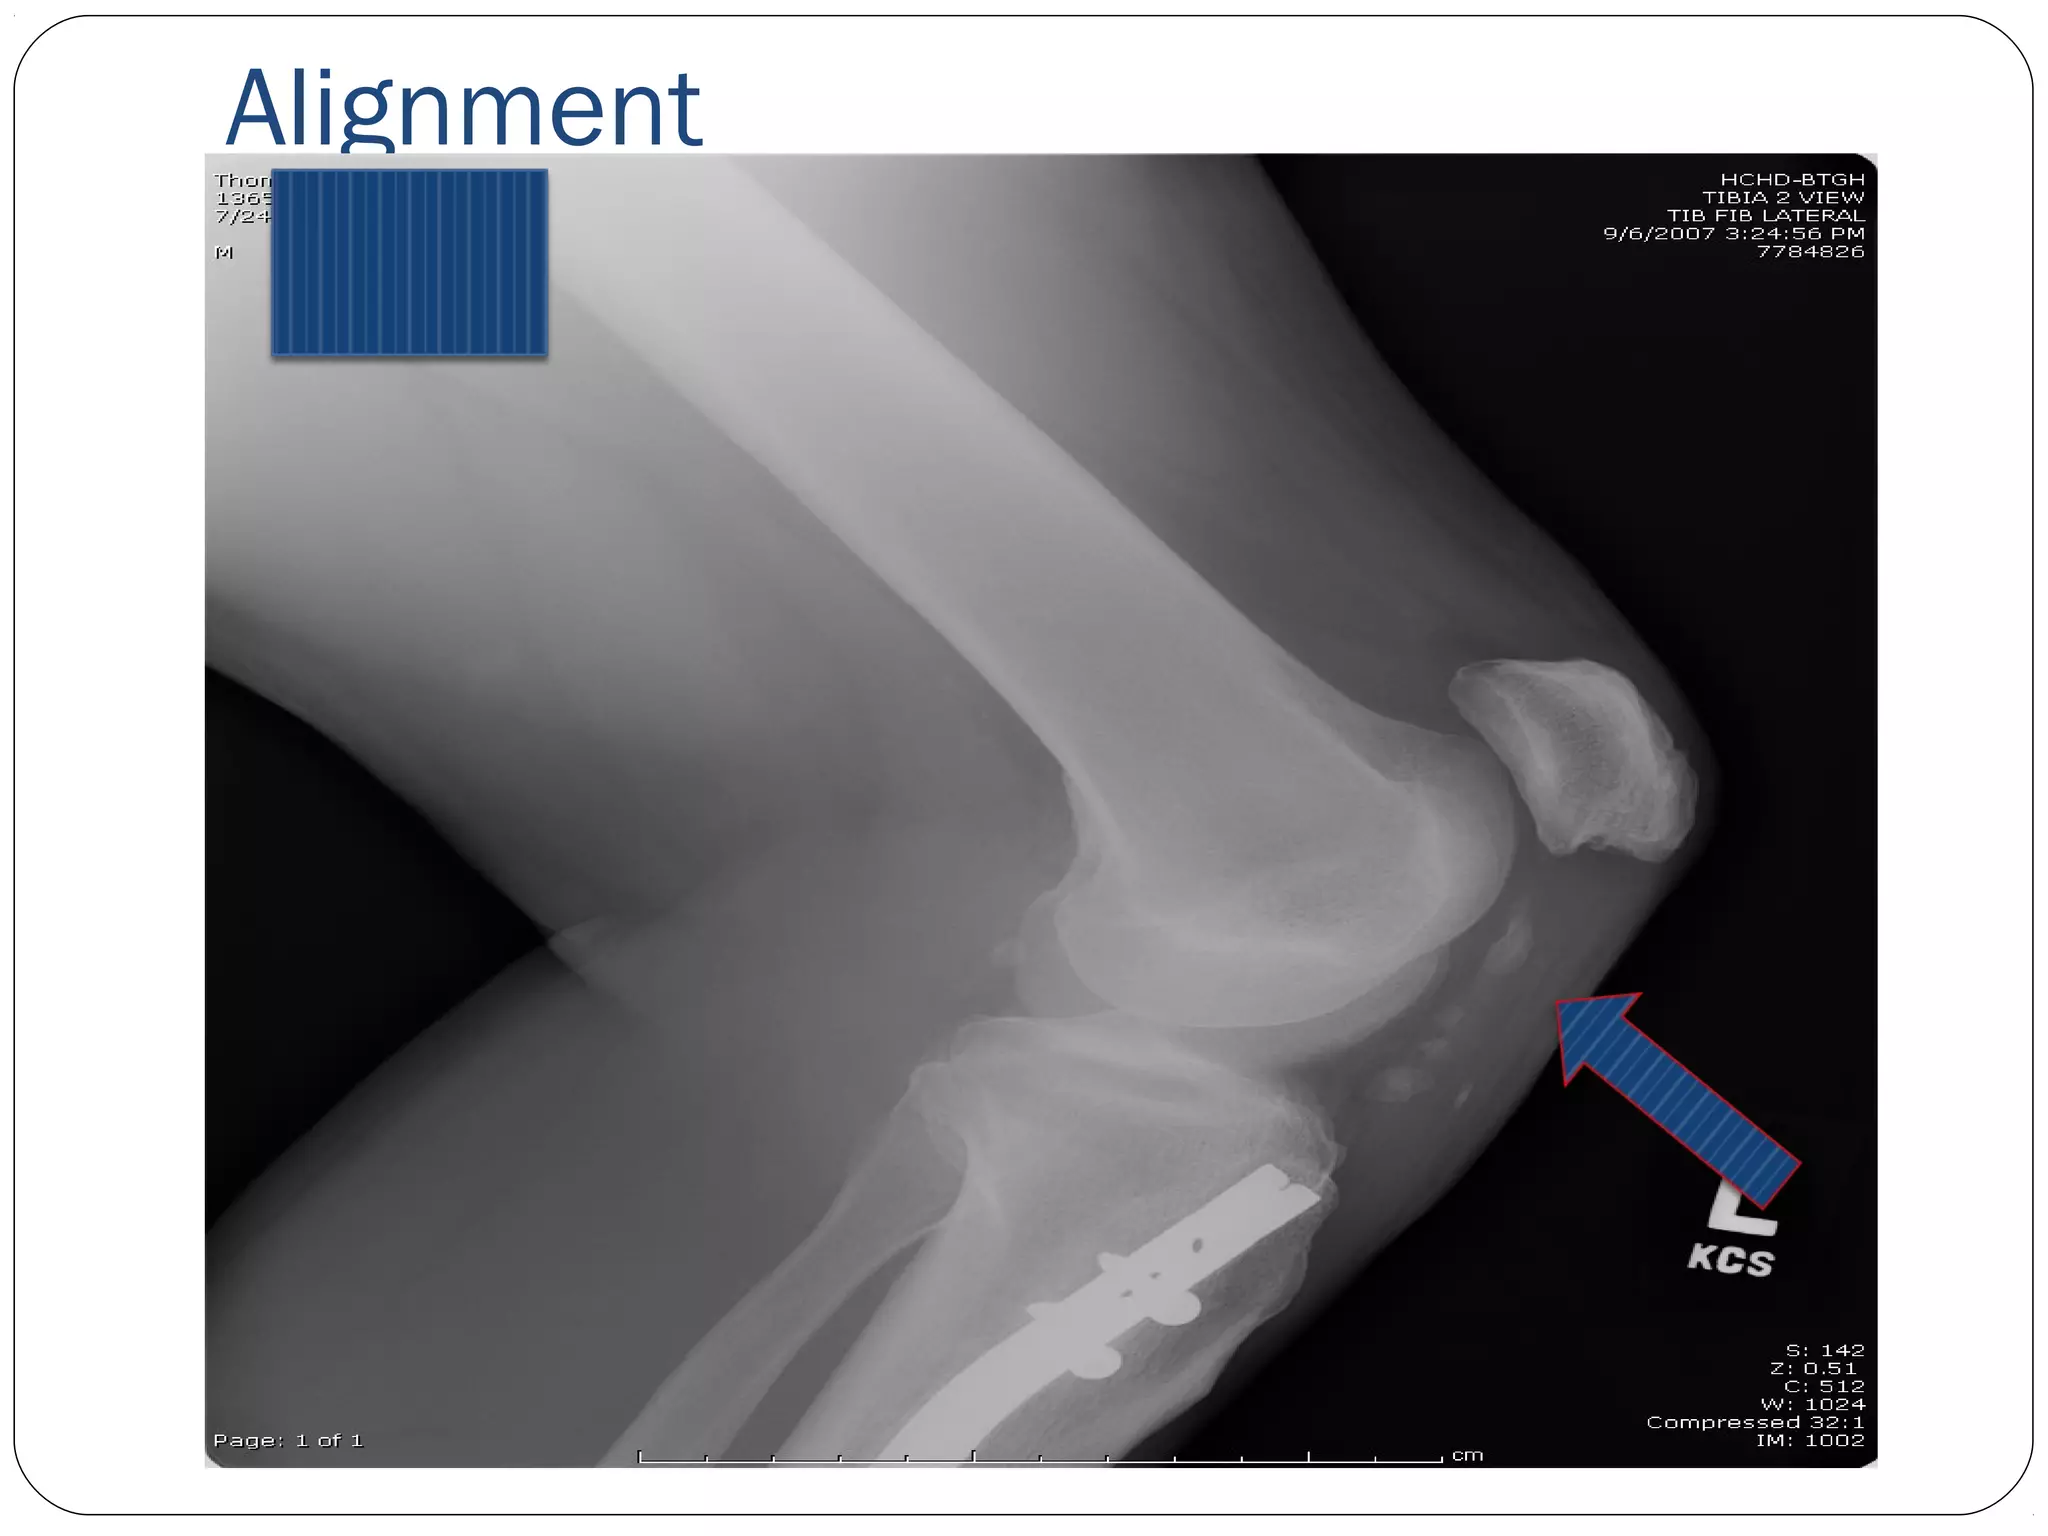

A-B-C-D

A- Alignment- is the bone in good general

alignment

B- Bone- general bone density

C- Cartilage- sufficient cartilage space

D- Dee other stuff??

Muscles, fat pads and lines, joint capsules,

miscellaneous soft-tissue findings, bullets